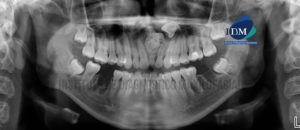

206 – Tercera molar retenida con hipercementosis radicular

Paciente de sexo femenino de 40 años de edad acude al Instituto de Diagnóstico Maxilofacial para evaluación imagenológica de terceras molares. A la evaluación de